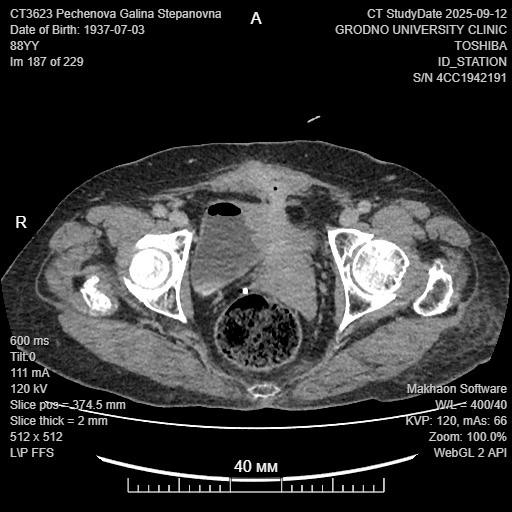

Первоначально восьмидесятивосьмилетняя гродненка, в анамнезе которой значился ранее перенесенный острый дивертикулит, с жалобами на ухудшения состояния здоровья обратилась к проктологу в консультативную поликлинику. Для постановки точного диагноза ей назначили колоноскопию, компьютерную и магниторезонансную томографию органов брюшной полости и малого таза, консультацию гинеколога и уролога. В ходе обширного обследования был обнаружен толстокишечно-влагалищно-маточно-мочепузырно-кожный свищ. Такие патологические сообщения (соустья) между несколькими органами являются относительно редкой, но довольно тяжёлой патологией, которая требует хирургического вмешательства. Для окончательного решения вопроса об операции был проведен консилиум с участием широкого круга специалистов, в том числе кардиологов, анестезиологов и реаниматологов.

Перед началом непосредственной операции исполняющий обязанности заведующего отделением урологии университетской клиники Даниил Василевич в рентген-урологической операционной выполнил пациентке эндоскопическое исследование мочевого пузыря, при котором четко визуализировал и показал коллегам хирургам и гинекологам локализацию свищей. Также с помощь рентгеноконтрастного исследования (фистулографии) он ясно продемонстрировал ход свища, который вовлекал прямую кишку, влагалище, матку, мочевой пузырь и кожные покроввы. Затем Диниил Михайлович осуществил катетеризацию специальными мочеточниковыми катетерами, что позволило четко визуализировать мочеточники и в ходе высокотехнологичного хирургического вмешательства предотвратить их травматизацию, несмотря на интимное вовлечение в инфильтративный процесс возле свища.